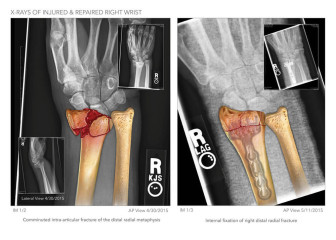

• Color Diagnostics®

• Personal Injury

• Project

• +2